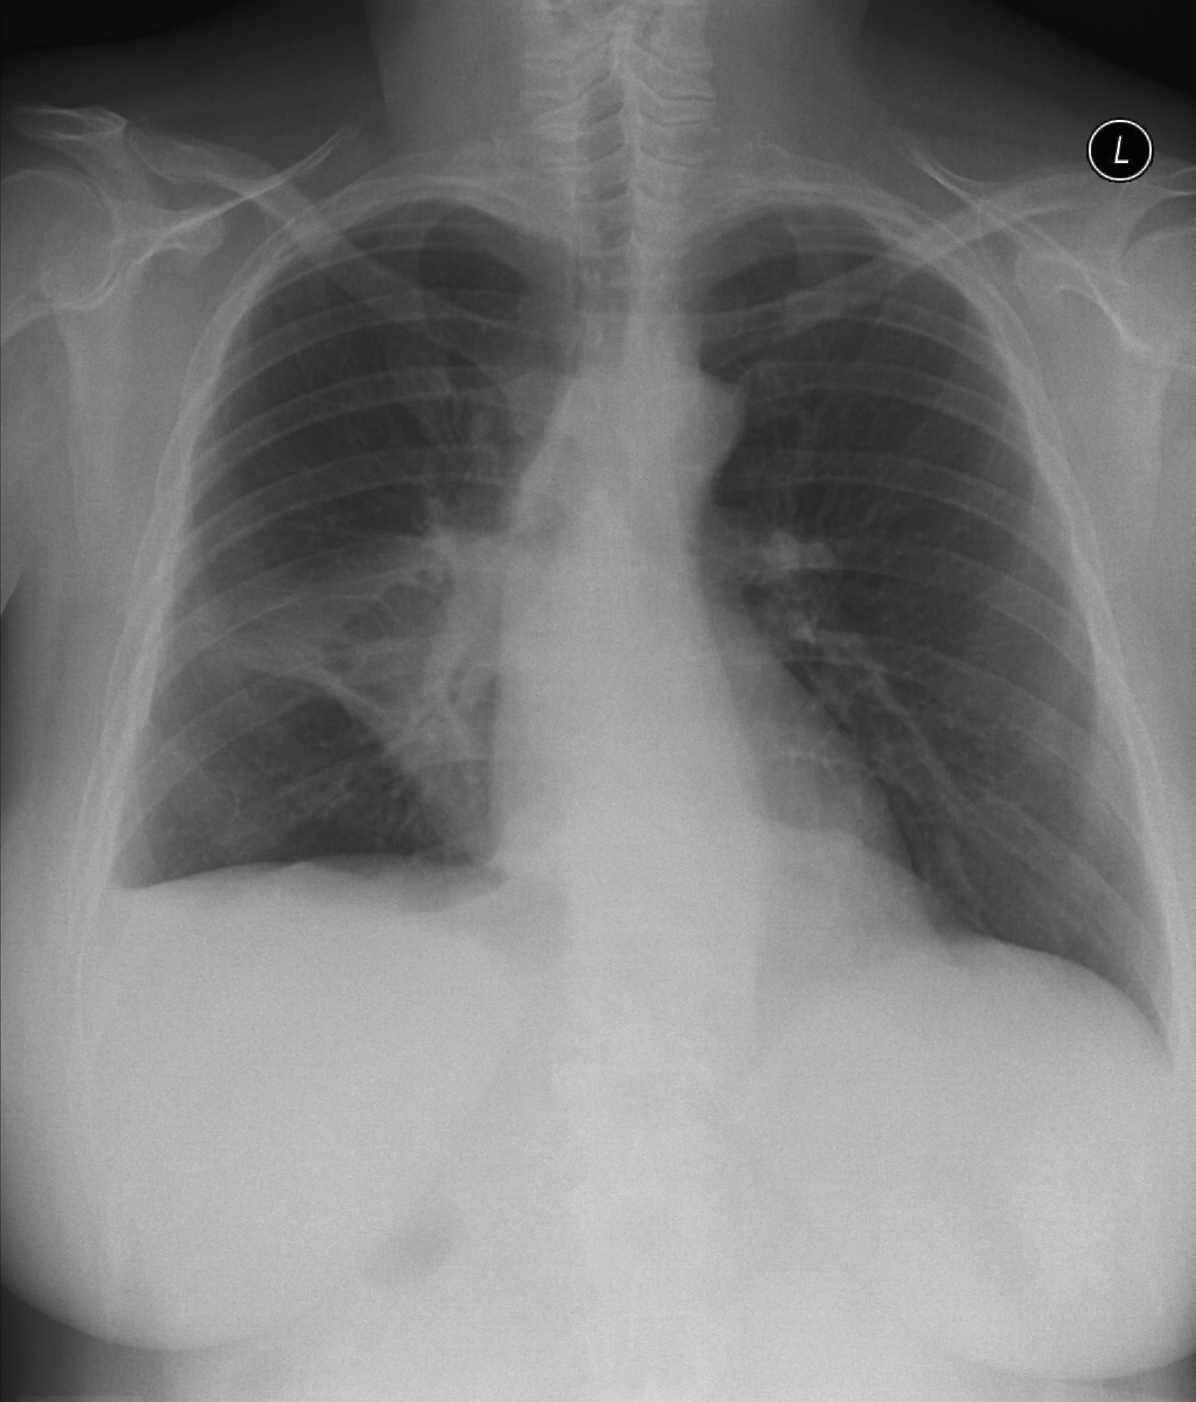

16. Right lobar pneumonia. a.) PA b.) lateral radiograph.